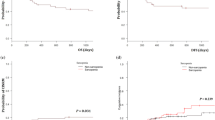

Of the 90 patients, 62 (78%) achieved CR within 2 cycles of induction chemotherapy. CR rate was significantly lower in patients with adverse cytogenetics than in those with favorable cytogenetics. CR rate was significantly lower in patients receiving less-intensive chemotherapy than in those with intensive chemotherapy. The CR rate was significantly lower in patients with body mass index (BMI) < 25 kg/m2 than in those with BMI ≥ 25 kg/m2. Patients with sarcopenia or adipopenia tended to show lower CR rates than patients without these conditions, but the difference was not significant (Table 2). Median follow-up was 13.8 months (range, 0.5–146.5 months). Three-year OS, EFS, and DFS in all patients were 53%, 35%, and 52%, respectively (Table 2). For sarcopenia and non-sarcopenia groups, 3-year OS was 35% and 67% (P < 0.001) and 3-year DFS was 25% and 58% (P < 0.0001), respectively (Fig. 1). For adipopenia and non-adipopenia groups, 3-year OS was 33% and 67% (P < 0.005), and 3-year DFS was 31% and 64% (P < 0.05), respectively (Fig. 2). Multivariate analysis showed an association between sarcopenia and lower OS (hazard ratio, 2.27; 95% confidence interval, 1.11–4.79; P < 0.05), with other prognostic factors of worse PS (≥ 2) (P < 0.05) and adverse cytogenetic risk (P < 0.05) (Table 3). Sarcopenia was also significantly associated with lower DFS (P < 0.0001) and lower EFS (P < 0.001). Patients with both sarcopenia and adipopenia exhibited the worst prognosis (Supplemental Fig. 2).

Next, we investigated the impact of sarcopenia in elderly patients (> 60 years old), who need careful assessment to decide treatment strategies. A total of 44 patients were > 60 years old (median age, 67 years; range, 60–84 years). Clinical characteristics are summarized in Table 4. Thirty-four patients (77%) showed PS 0 or 1, and 48% received intensive chemotherapy for induction. Reasons for receiving less-intense chemotherapy were age (n = 10), comorbidities (n = 7), and hypoplastic bone marrow (n = 4). The cutoff value for SMI used to identify sarcopenia was defined as < 42 cm2/m2 in males and < 32 cm2/m2 in females according to ROC analysis of elderly patients. Nine patients (20%) were defined as showing sarcopenia. Sarcopenia was seen in 12% of patients with PS ≤ 1 and 50% of patients with PS ≥ 2 (P < 0.05). Three-year OS was 0% for the sarcopenic group and 49% for the non-sarcopenic group (P < 0.0005), 3-year DFS was 0% and 61% (P < 0.0001), and 3-year EFS was 0% and 46% (P < 0.005), respectively (Fig. 3). Causes of death in sarcopenia patients were leukemia (n = 8) and infection (n = 1). Causes of death in non-sarcopenia patients were leukemia (n = 9), pulmonary hemorrhage (n = 1), acute graft-versus-host disease (n = 1), and pancreas cancer (n = 1).